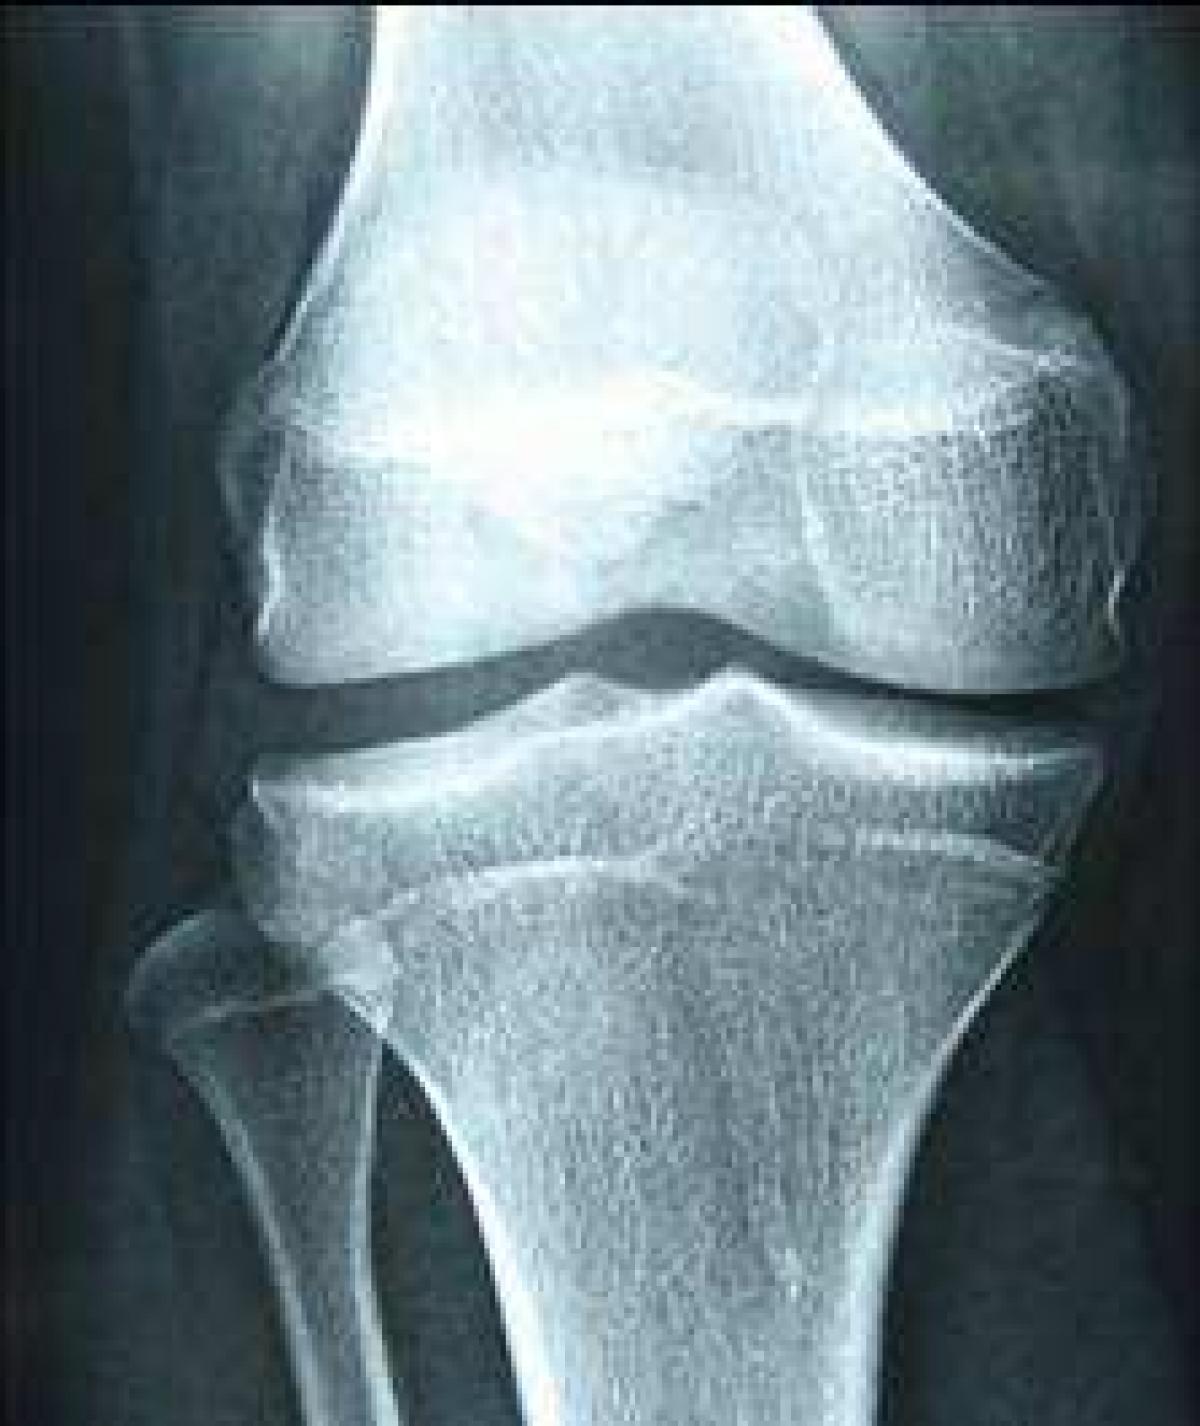

半月板损伤很常见,在多数情况下半月板损伤会有急性受伤史。比如在对抗激烈的足球、篮球、羽毛球等运动中,通常情况下,发生在膝关节屈曲同时伴有旋转发力的动作中。

得了半月板损伤会有哪些症状?

一、膝关节剧痛尤其是受伤后,膝盖伸不直,疼痛比较的剧烈,位置较固定。

二、肌肉无力双腿经常发软,感到肌肉无力,当上下台阶的时候,这种现象更加的明显,控制不了关节。

半月板损伤的危害:

1、活动受限半月板损伤发生后,有关节充血肿胀,疼痛的症状出现,下蹲都成问题,功能受到限制。